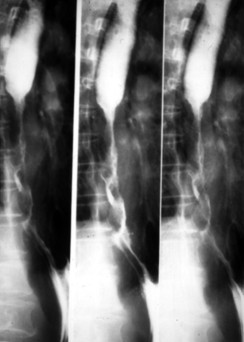

Carcinome

epidermoide : forme stenosant circoferentielle .

Image TOGD mono de contrast |